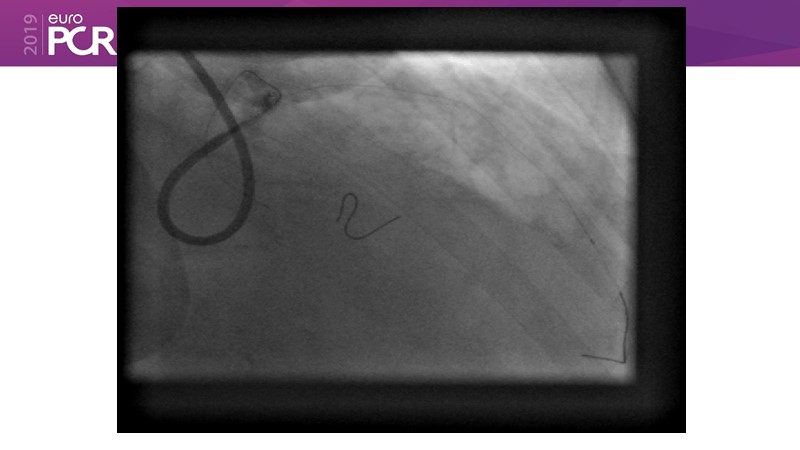

Go implant-free in de novo lesions: DCB-only strategy

Consult this session to learn about the DCB-only concept, treatment methodology and consensus group recommendations, and discover the latest scientific evidence of DCB-only in de novo lesions and in complex PCIs.